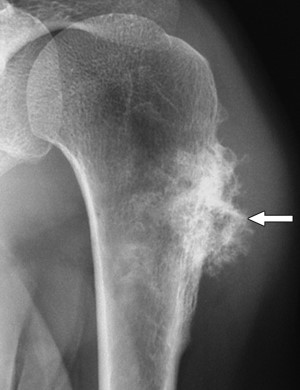

На рентгене эта опухоль похожа на вдавливание в форме блюдца и склерозированным краем в пораженной кости. Иногда также отмечают частично разрушенную кортикальную пластинку. В этом случае границы опухоли с окружающей костью становится неопределенной и расплывчатой. В месте, где опухоль соприкасается с непораженной частью кости в большинстве случаев видна треугольная склеротическая шпора.

Периостальная саркома чаще образуется у детей, чем у взрослых. Она отличается тем, что ее плоский по форме узел пронизан тонкими «спикулами» и имеет участки околокостного патологического костеобразования в виде уплотнений по форме похожих на облака или хлопья.